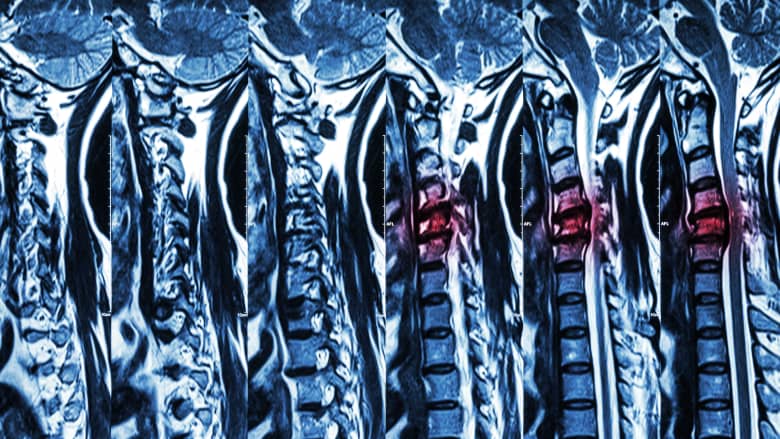

Magnetic resonance imaging (MRI) is used when high-resolution images of the body’s tissues are required for diagnosis and treatment.

For back or neck pain, MRI scans are a preferred diagnostic tool for investigating musculoskeletal problems with or without neurologic deficits when previous imaging is suggestive of spinal pathology. However, the presence of certain implants or prostheses may interfere with the MRI process, making it a health risk.

Severe spinal cord compression is evaluated in detail on an MRI scan.

An MRI scan may be used to diagnose, further investigate, and/or plan the treatment of neck pain or back pain that fulfills one or more of the following criteria: